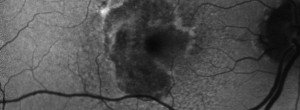

Drusen Ooze: A Novel Hypothesis in Geographic Atrophy